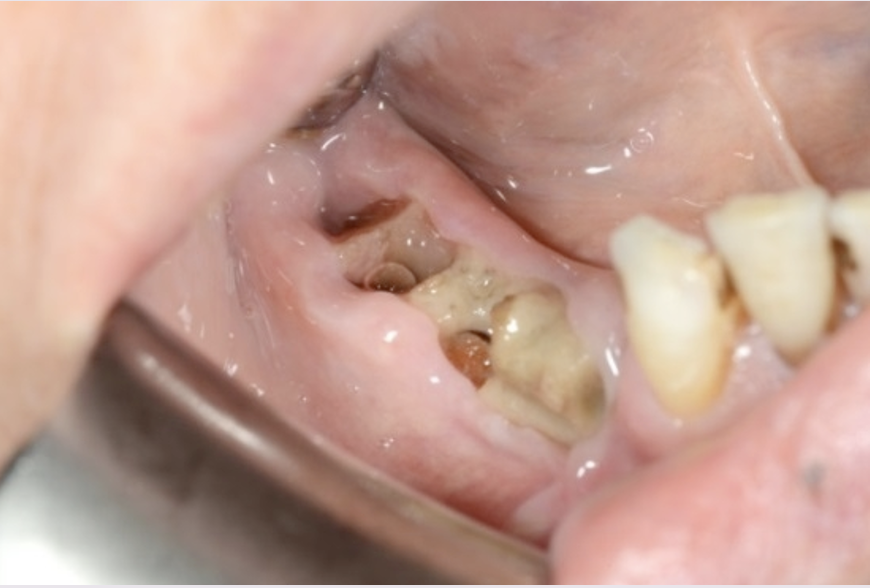

What is stage 1 MRONJ?

What is the treatment?

A

Asymptomatic exposed bone

Analgesics and antibiotics

Antiseptic mouthwash